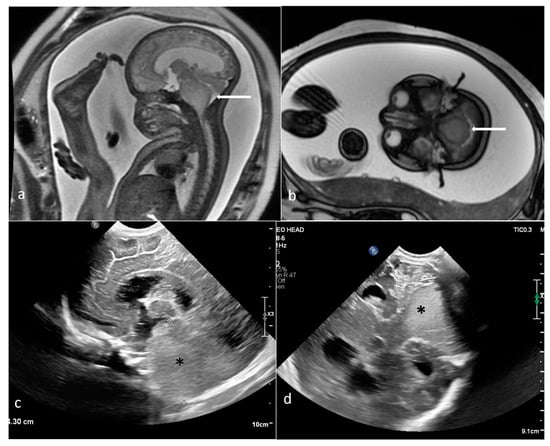

| Mesoblastic nephroma | kidney | 2 | 98.4 [42.9–153.9] | yes (1100–1310) | Solid | 0/2 | yes (1/2) |

| Wilms tumor | kidney | 1 | 366.9 | yes (548) | Mixed | N/A | yes (solid part) |

| Renal | 5–7 | 66% mesoblastic nephroma |